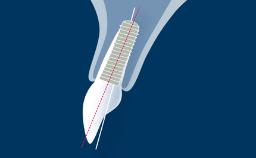

Surgical Planning and Procedures

Saving or Replacing Implants

Congress Lecture